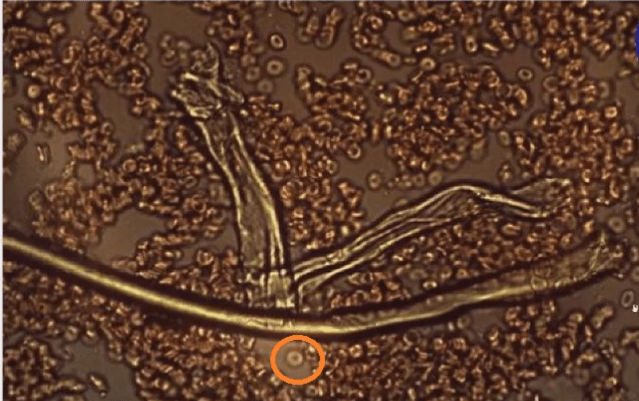

Nästa bild är på en person som har injicerats med det experimentella Covid-läkemedlet. Blodet koaguleras, de missformade röda blodkropparna klumpas ihop. Cellen som är inringad i bilden är en frisk röd blodkropp, en av de få på bilden, som sitter bredvid grafenfibrerna. Du kan se storleken på grafenfibrerna i förhållande till storleken på en röd blodkropp. Fibrer av denna storlek kommer att blockera kapillärer. Du kan också se att grafenfibrerna är ihåliga och innehåller röda blodkroppar.